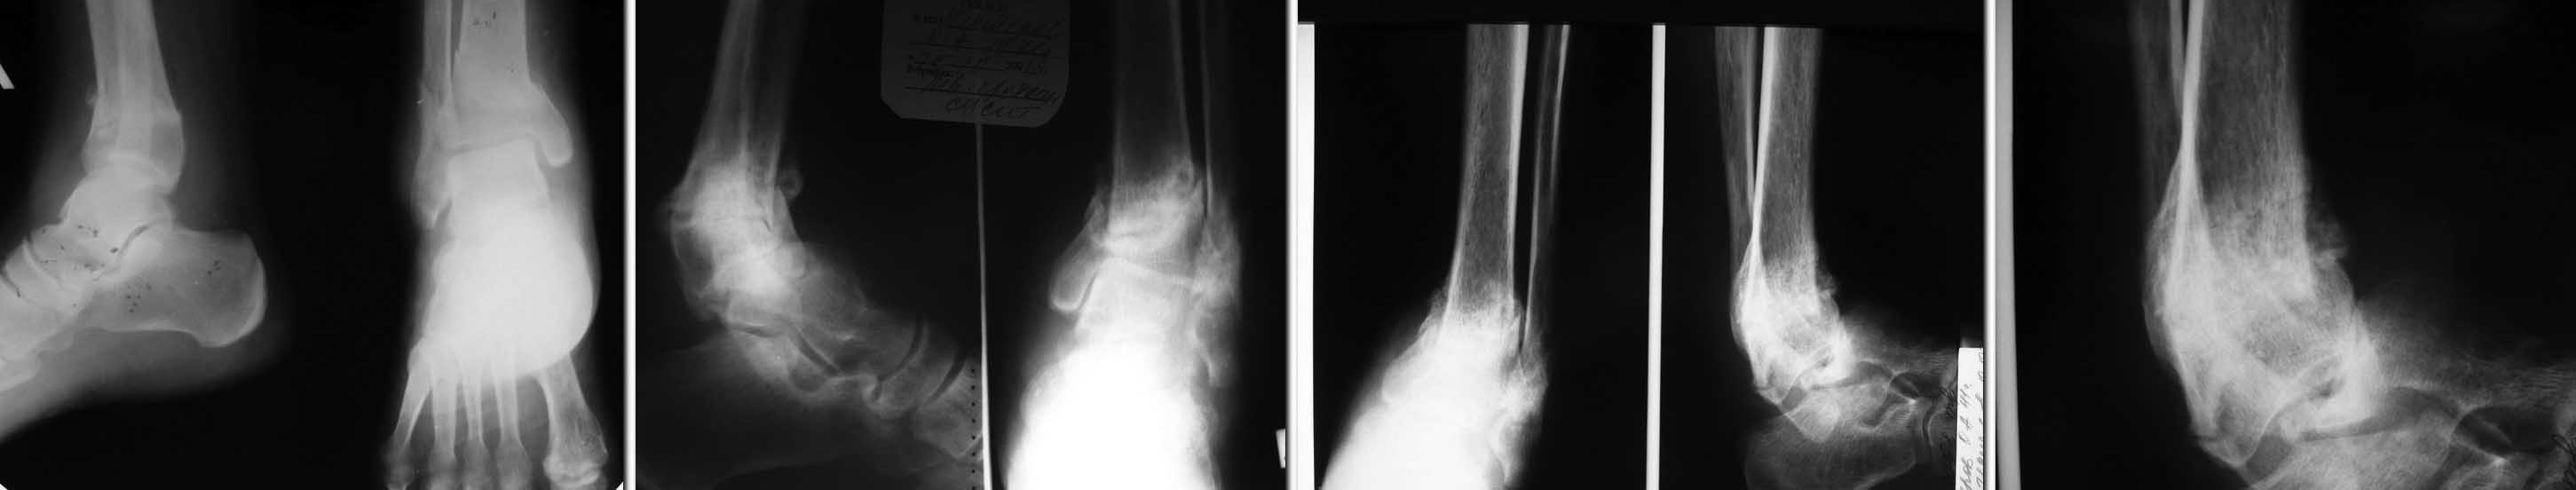

Пациент 40 лет,   получает в течение 5 лет постоянно терапию ГКС по поводу саркоидоза легких и болезни  Бехтерева .

в начале лета сего года подвернул ногу. Появились умеренные боли при ходьбе, постепенно усиливались, через пару недель обратился в поликлинику к хирургу.  Выполнена р-графия (1 снимок) Выявлен перелом, рекомендовано "ходить потихоньку с тростью"  (со слов пациента). В октябре повторное обращение и контрольная р-графия из за усиления болей - выявлен ложный сустав,

(снимок 2 ) Пациент начал ходить по консультантам. К нам обратился к декабрю, боли усилились значительно. Р-логически - полный передний вывих стопы (последняя пара рентгенограмм), однако пациент ходит с тростью.

Мне кажется, что в данном случае причиной патологического переднего вывиха стал асептический некроз таранной кости.

Следует выполнить корригирующий артродез из наружного чрезлодыжечного  доступа (с остеотомией выше зоны ложного сустава). В зону клиновидной резекции включить некротизированную таранную кость. Если после резекции от таранной кости ничего не останется - выполнить большеберцово-пяточный артродез, укрепить его спереди оставшейся частью таранной кости, снаружи - наружной лодыжкой. Фиксация в аппарате Илизарова.

Ложный сустав консолидирует в процессе фиксации. Главное выставить правильное положение стопы.

Проблемы со сращением будут.